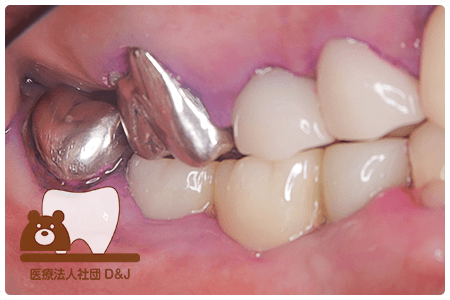

症例1フルジルコニアクラウン 左下6

治療前

治療後

55歳 男性

- 治療内容

- メタルクラウンを除去し虫歯治療後にフルジルコニアクラウンを装着しました。

- 治療期間

- 2カ月半

- 費用

- 自費

フルジルコニアクラウン:77,000円(税込)

(R8.2月時点)

- その他の治療の費用は含まれておりません。

- リスク・副作用

- 強い力が加わると割れる可能性があります。また、噛み合わせや歯ぎしりの影響で脱離することがあります。